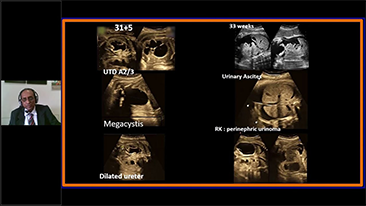

L'ottimizzazione dei flussi di lavoro in ambito ostetrico e ginecologico ├© necessaria per completare grandi volumi di visite di screening per la salute delle donne. Ad esempio, le malformazioni del sistema nervoso centrale (SNC) sono una delle anomalie congenite pi├╣ comuni. A causa di varie circostanze che limitano l'accuratezza delle immagini, come la posizione poco adeguata del feto, l'MSP ├© particolarmente difficile da rilevare tramite l'ecografia 2D. Pertanto, il rilevamento e le misurazioni automatizzate possono migliorare notevolmente l'efficienza della scansione.